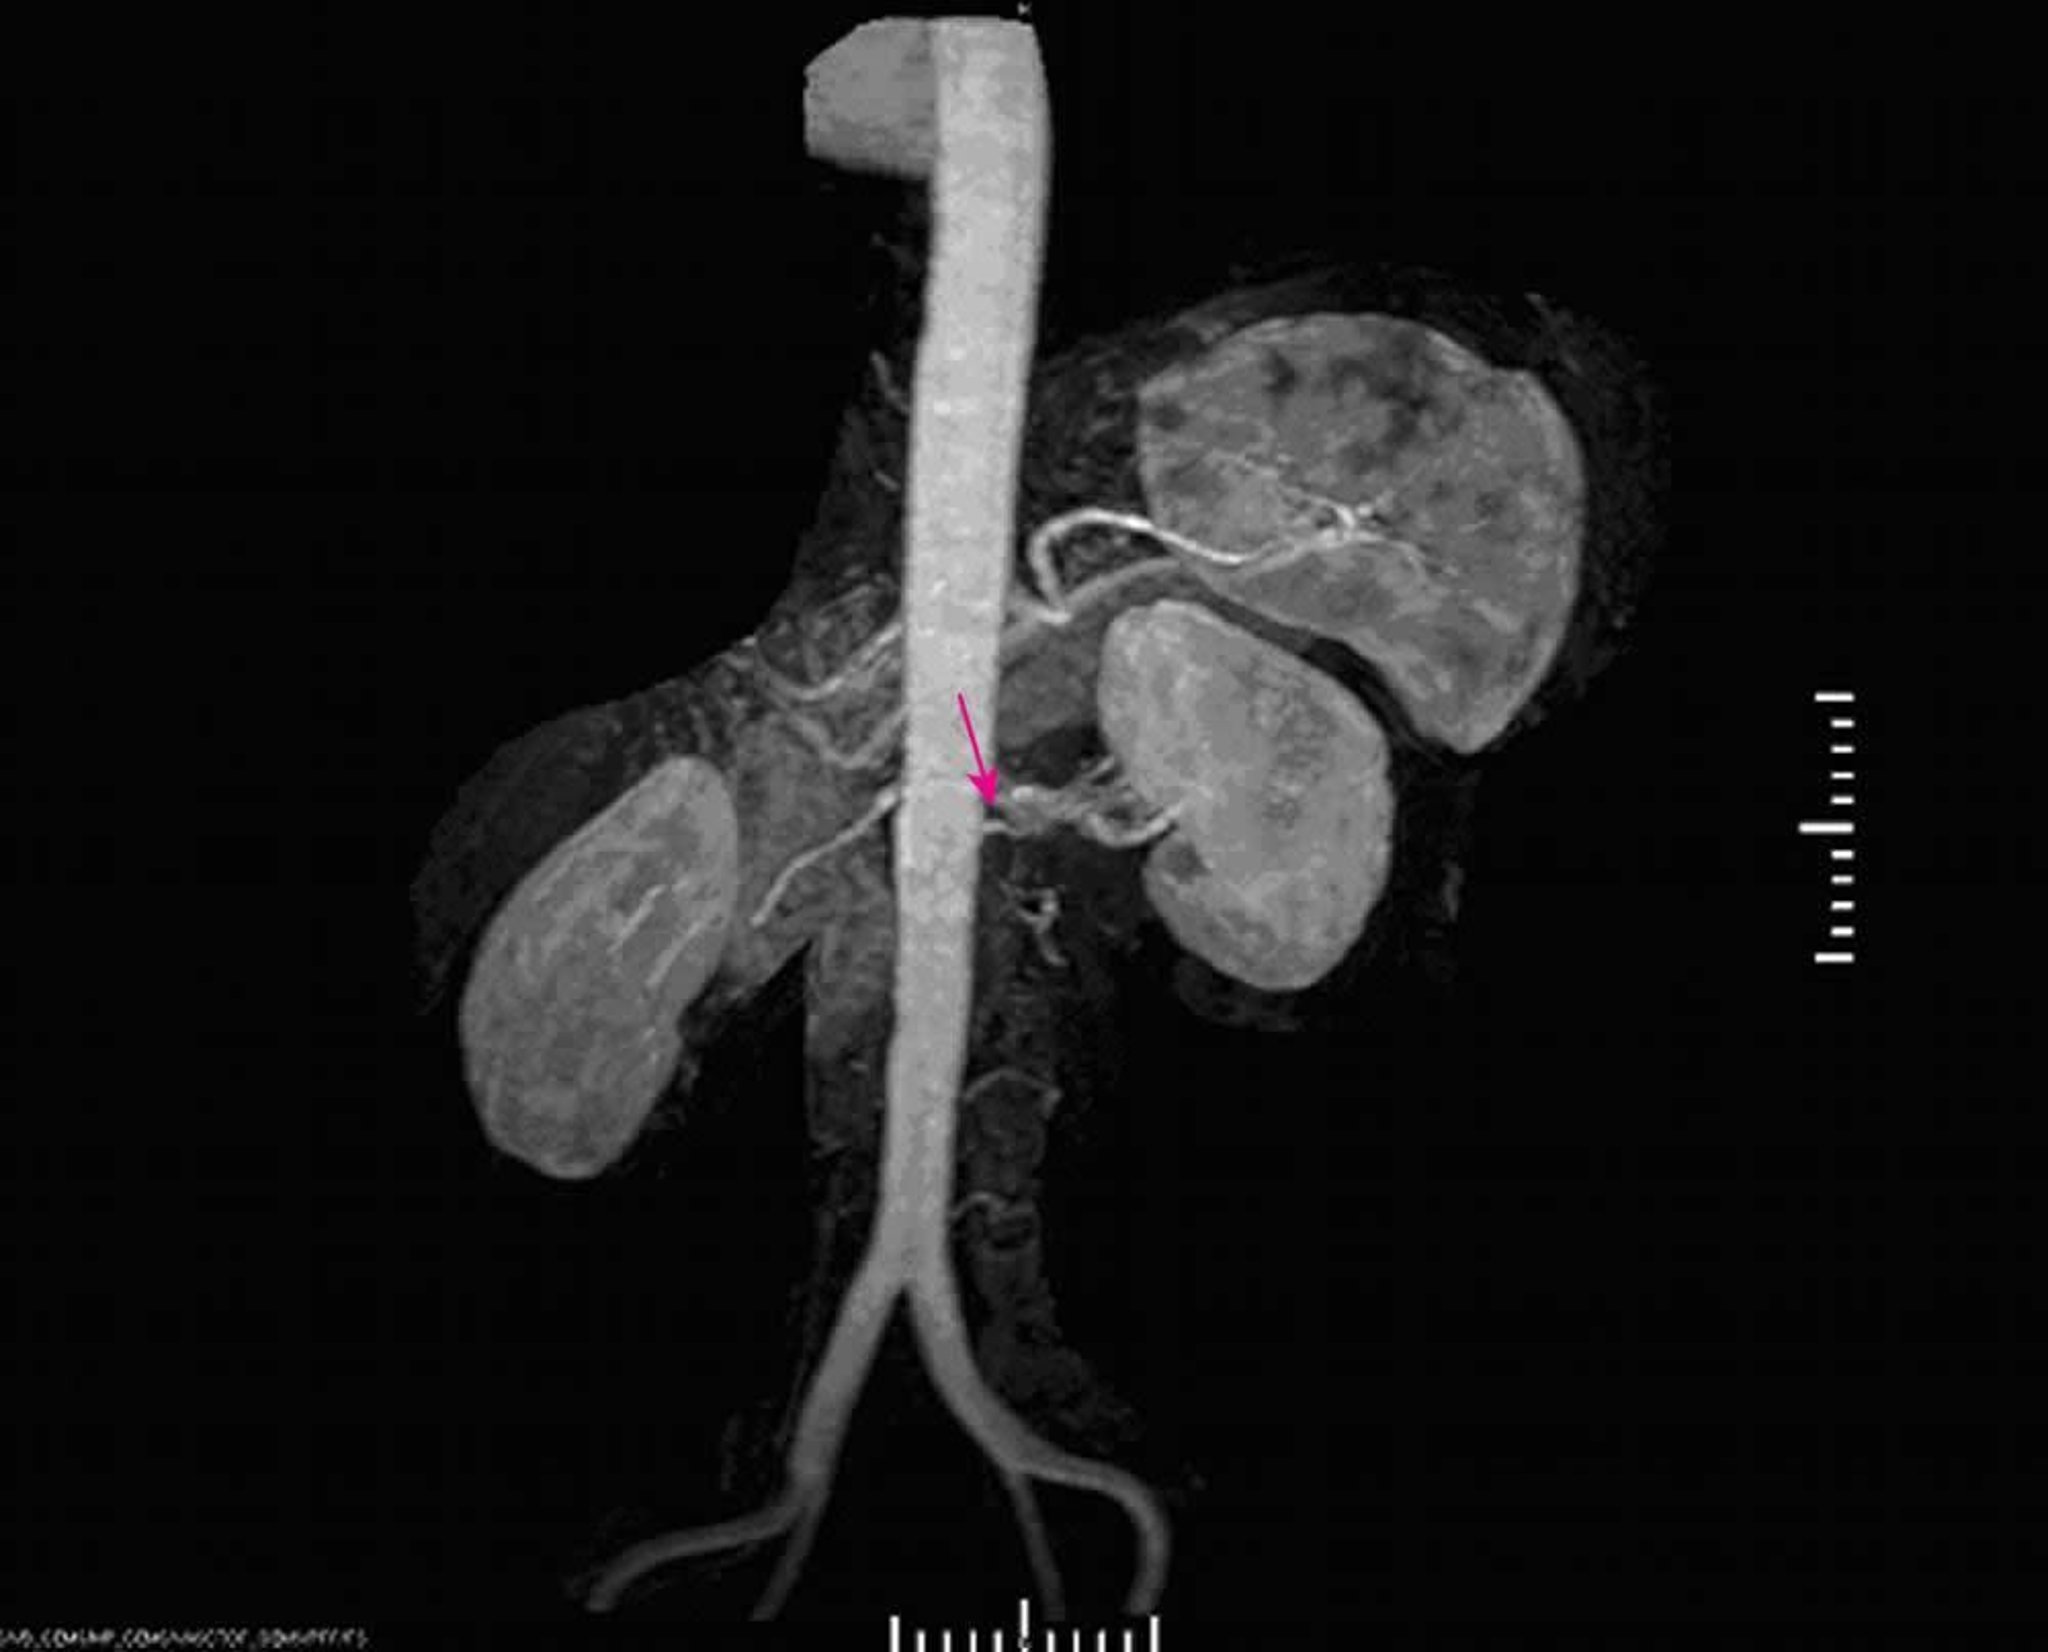

Renovascular Hypertension (Magnetic Resonance Angiography)

Magnetic resonance angiography demonstrates severe stenosis at the origin of the left main renal artery.

Image provided by Jan N. Basile, MD.